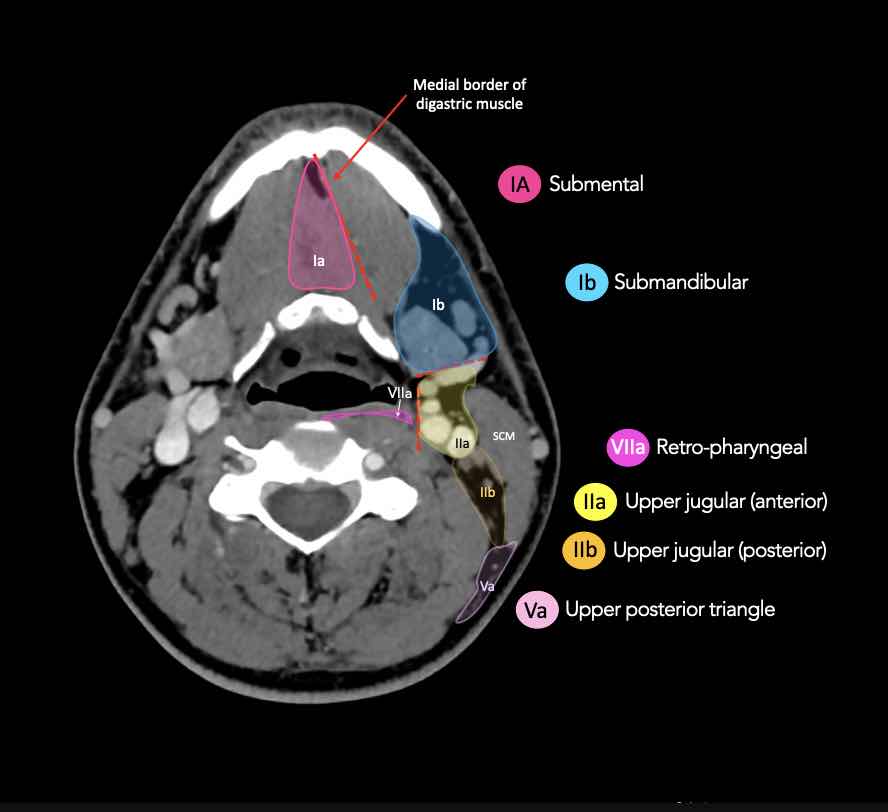

CT Scan Mặt Cắt Ngang (Axial CT)

Các lát cắt CT mặt phẳng ngang tương ứng với hình minh họa tổng quan.

Các lát cắt CT mặt phẳng ngang với hình ảnh chi tiết hơn.

Nhấp vào hình ảnh để phóng to.

I – Dưới cằm và dưới hàm

Các hạch bạch huyết ở tầng I có nguy cơ phát triển di căn từ các ung thư khoang miệng, hốc mũi trước, mô mềm vùng mặt giữa và tuyến dưới hàm.

Tầng Ia

là vùng giữa nằm giữa bụng trước của các cơ nhị thân, chứa các hạch dưới cằm.

Tầng Ib

chứa các hạch dưới hàm nằm trong khoang giữa mặt trong của xương hàm dưới ở phía ngoài và cơ nhị thân ở phía trong, từ khớp mu cằm ở phía trước đến tuyến dưới hàm ở phía sau.

II – Tĩnh mạch cảnh trên

Tầng II nhận bạch huyết hướng tâm từ mặt, tuyến mang tai, và các hạch dưới hàm, dưới cằm và sau hầu.

Tầng II cũng nhận trực tiếp các bạch mạch thu thập từ hốc mũi, hầu, thanh quản, ống tai ngoài, tai giữa, và các tuyến dưới lưỡi và dưới hàm [1].

Tầng II có thể được chia thành tầng IIa và tầng IIb bằng cách vẽ một đường tại bờ sau của tĩnh mạch cảnh trong.

Các hạch bạch huyết ở tầng IIa và IIb có nguy cơ chứa di căn từ các ung thư hốc mũi và khoang miệng, vòm hầu, hầu miệng, hạ hầu, thanh quản và các tuyến nước bọt lớn.

Tầng IIb thường liên quan hơn đến các khối u nguyên phát ở hầu miệng hoặc vòm hầu, và ít thường xuyên hơn với các khối u ở khoang miệng, thanh quản hoặc hạ hầu [1].